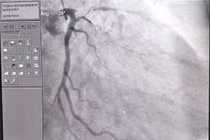

Trái với phẫu thuật bắc cầu nối chủ vành cần mở lồng ngực, can thiệp động mạch vành có thể thực hiện chỉ bằng cách mở một lỗ nhỏ trên da để đưa catheter vào động mạch ở đùi hay cổ tay.

Hẹp lòng động mạch vành sẽ gây ra tình trạng thiếu máu cơ tim, tình trạng này nếu kéo dài lâu ngày, bệnh nhân sẽ bị đau ngực, suy tim, rối loạn nhịp tim và nguy cơ bị nhồi máu cơ tim cấp.